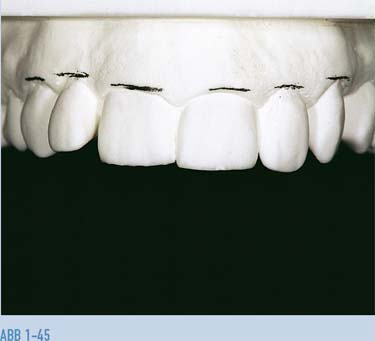

Abb. 1-45 Die Gingivakontur ist hier vom Techniker markiert; dies zeigt die unvollständige Extrusion der klinischen Kronen an den zentralen Schneidezähnen und die unnormale Position der seitlichen Schneidezähne in Relation zu ihren Nachbarzähnen.